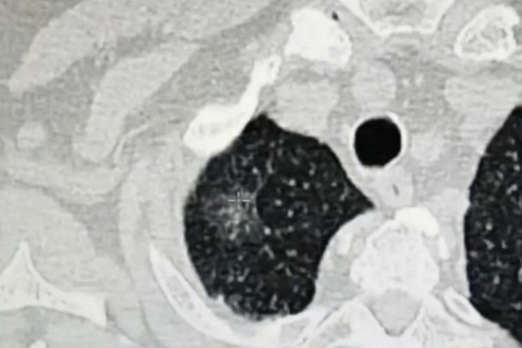

磨玻璃包裹着小的实心区,大小多在5~10mm。

结节的实性成分占比超过50%,磨玻璃成分减少,甚至大部分是实性结节,大小多≥10mm。